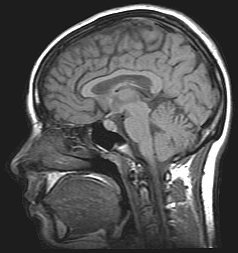

Neuroimaging, usually with computed tomography (CT) or magnetic resonance imaging (MRI), is used to exclude any mass lesions. In IIH these scans typically appear to be normal, although small or slit-like ventricles, dilatation and buckling[13] of the optic nerve sheaths and "empty sella sign" (flattening of the pituitary gland due to increased pressure) and enlargement of Meckel's caves may be seen.

An MR venogram is also performed in most cases to exclude the possibility of venous sinus stenosis/obstruction or cerebral venous sinus thrombosis.[5][7][8] A contrast-enhanced MRV (ATECO) scan has a high detection rate for abnormal transverse sinus stenoses.[10] These stenoses can be more adequately identified and assessed with catheter cerebral venography and manometry.[11] Buckling of the bilateral optic nerves with increased perineural fluid is also often noted on MRI imaging.